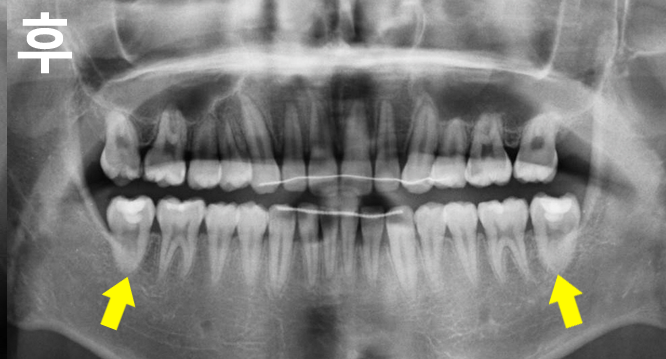

심한 어금니 매복으로 인해 내원하셨습니다.

부분교정으로도 해결할 수 있었으나 앞니 비뚤함도 개선 원하시어 전체교정으로 진행하였으며

교정 후 매복치가 올바르게 배열된 것을 확인할 수 있습니다.

매복치교정은 뽑고 임플란트를 하는 방법보다 잇몸뼈와 내 치아를 보다 많이 보존할 수 있기 때문에 조기에 치료해주는 것이 바람직합니다.